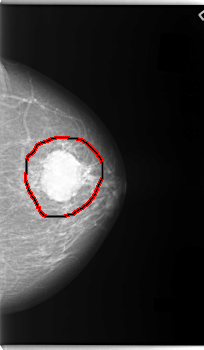

FILE: C_0088_1.LEFT_MLO.OVERLAY

TOTAL_ABNORMALITIES 1

ABNORMALITY 1

LESION_TYPE MASS SHAPE OVAL MARGINS MICROLOBULATED

ASSESSMENT 5

SUBTLETY 5

PATHOLOGY MALIGNANT

TOTAL_OUTLINES 1

BOUNDARY